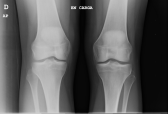

Un rayo X es una imagen creada en varios tonos de negro, gris y blanco. Los huesos y otras estructuras calcificadas aparecen casi blancas, ya que son mucho más densas que el tejido blando y absorben mayor cantidad de radiación electromagnética. El músculo, la grasa y otros tejidos blandos aparecen en tonalidades más oscuras (desde el negro hasta diferentes tonos de gris).

Este tipo de tecnología se emplea en hospitales, clínicas, centros de imagen y consultorios médicos. Para su conveniencia, en ANTA SALUD tomamos todas las radiografías en nuestras instalaciones. Ellas nos ayudan a diagnosticar fracturas vertebrales, escoliosis, espondilosis, formación de espolones óseos (osteofitos), espondilolistesis y otros trastornos de la columna, etc.